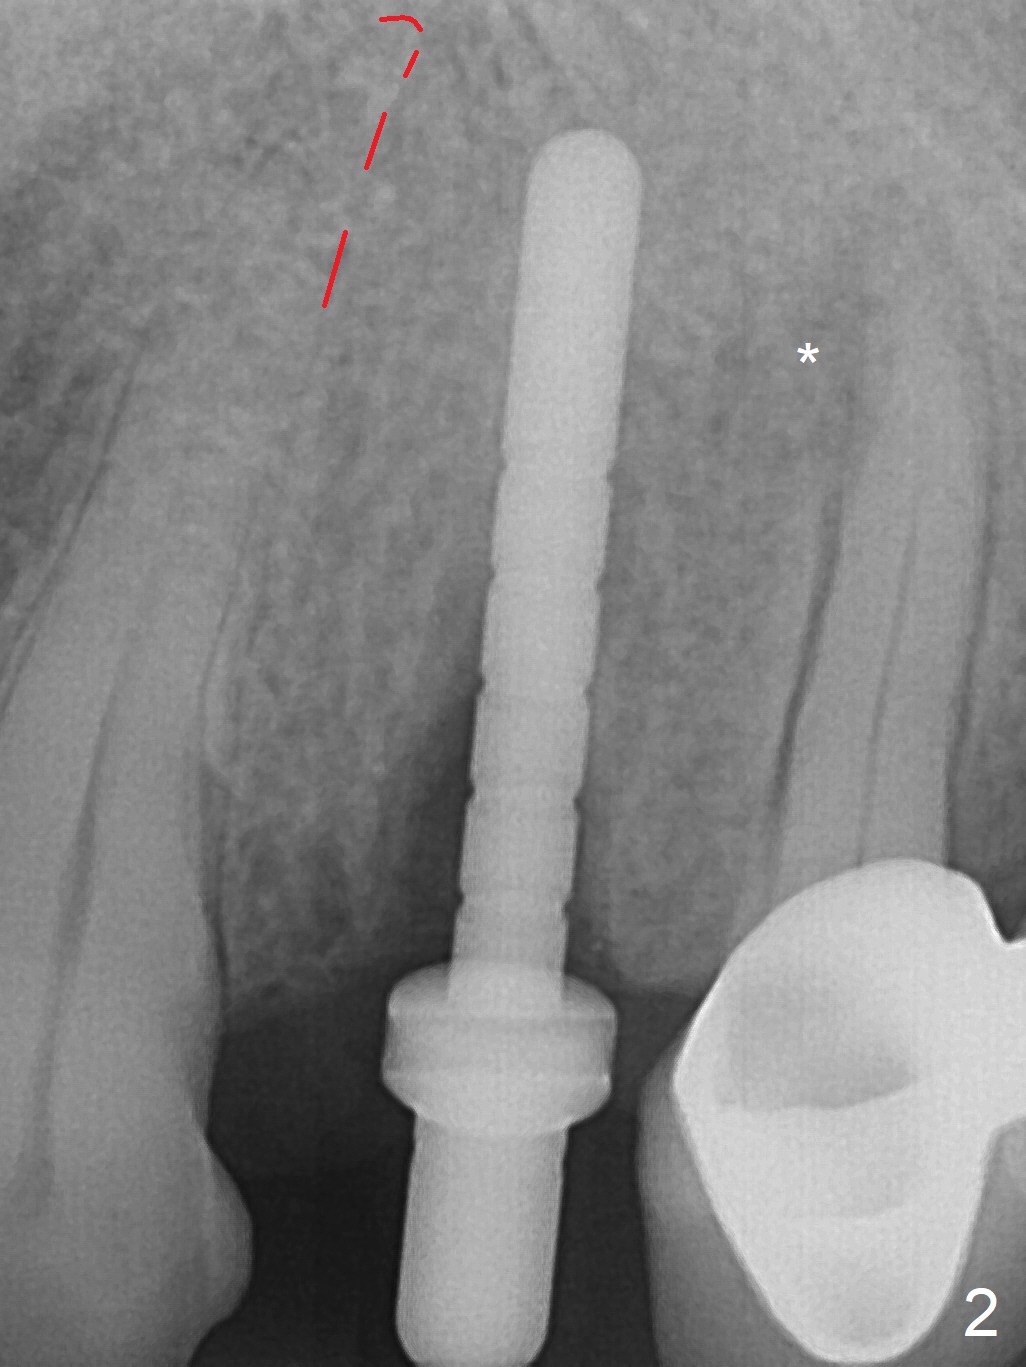

After extraction of the oval-shaped residual roots at #12 (Fig.1), osteotomy is initiated in the palatal socket for 18 mm; since the root of the canine curves distal (Fig.2 red dashed line), the osteotomy cannot afford to move mesial and extend more apical. A 3.8x15 mm implant is placed with > 50 Ncm (Fig.3). With immediate placement of a 4.5x4(3) mm abutment, an immediate provisional is fabricated to close the sockets (Fig.4 P). The provisional has clearance from the RPD clasps (Fig.5). In fact the implant could be longer, as shown by immediately postop panoramic X-ray (Fig.6). The implant seems to be osteointegrated 3 months postop (Fig.7). The tooth #13 is symptomatic with caries (Fig.8 C) 7 months post #12 crown cementation; the #13-15 FPD dislodges. The upper left quadrant is cold and hot sensitive 2.5 months post RCT (Fig.9); although there is mild percussion at #13, pulpal test shows that the tooth #15 has lingering pain. The FPD was recemented temporarily after RCT; it cannot be removed. The implant crown has been loose for several months during the pandemic before he returns 2 years 7 months post cementation. In fact the abutment has been not seated completely (from Fig.3 to 9). The crown/abutment is removed from the mouth; the crown is sectioned and separated from the abutment; the latter is reseated, but incompletely (Fig.10 <). With suspicion of the mesial crestal contact, profile drills 4.6 and 5.5 mm are used without effect. A new (old probably being worn) and longer (easy to turn in the narrow space) abutment is finally seated completely (Fig.11 (no gap)). After occlusal adjustment, abutment level impression is taken for a new crown.